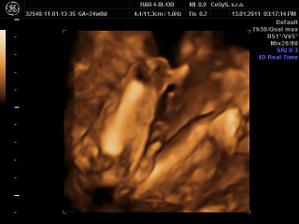

Naša lásočka 13+0tt...už teraz ju milujeme!)))